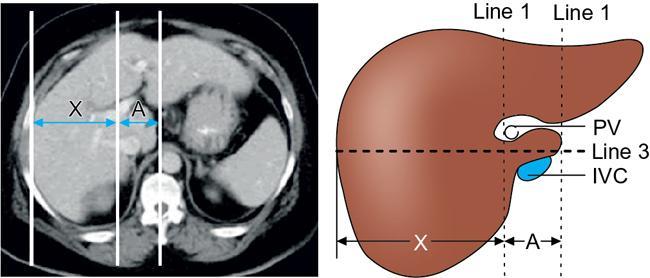

Ritu K. Kashikar, Shrinivas B. Desai Knowledge regarding normal dimensions of organs is important as visceromegaly is the first and often only abnormality in a variety of disorders. The radiologist should also be aware of normal diameters of vessels and ducts because an increase in size is usually a pointer to pathology in the organ. This chapter is a lucid review of normal sizes of organs, vessels, duct and also focuses on which section and location should size be measured to avoid interobserver variation. The liver is the largest organ in the abdomen. Hepatomegaly is a common condition and often the first clinical and imaging feature of various disorders. It is hence imperative for the radiologist to know the normal size and the section on which measurements should be taken. USG is commonly used to measure liver size. The longitudinal view is commonly used to measure liver size. The liver is considered normal in size if on longitudinal scan through the midhepatic line the liver measures 13 cm or less. This is true in approximately 93% individuals Measurement more than 15.5 cm suggests hepatomegaly in 75% cases (Figs. 9.3.1 and 9.3.2) (Table 9.3.1). Hepatomegaly is also suggested by an inferior angle of more than 45 degrees in the left lobe and more than 90 degrees in the right lobe. The normal liver measures approximately 6.5 cm first 3 months of age and reaches a size of 12.5 cm by 10–12 years of age. Liver size can be measured on unenhanced or enhanced CT. On CT the liver measures 10–12.5 cm in the midclavicular line on an average. A liver measuring more than 15.5–16 cm in the midclavicular line is considered enlarged. The midclavicular line measurement is done in coronal plane (Fig. 9.3.3). Another important measurement is the size of caudate lobe. The caudate to right lobe ratio (C/RL) is a measurement used to diagnose caudate lobe hypertrophy and right lobe atrophy which is important in the diagnosis of cirrhosis. The axial section immediately below main portal vein bifurcation is used for measurements. The following lines are drawn on the liver (Fig. 9.3.4). C/RL: In an adult patient of average weight (60 kg), the estimated liver volumes can range from 1024–1302 cm3 (Fig. 9.3.6). USG and Doppler provide important information regarding patency of artery in postoperative/transplant setting. Normal hepatic artery waveform is pulsatile and of low resistance. The normal resistive index measures 0.7. High or low resistivity index (RI) indicated pathology. The measurements of the hepatic arteries bare importance in transplant imaging. The diameter and length of the arteries are best measured on CT angiogram images. Arteries smaller in calibre than 2 mm may be difficult to anatomize. Replaced RHA is often longer in length than standard arteries. The normal diameters of the hepatic arteries are mentioned in Table 9.3.2 (Figs. 9.3.7–9.3.9). The portal venous system is valveless and hence its diameter is influenced by respiratory variations. The portal venous diameter is greatest during inspiration and hence all measurement should be made in this phase (Table 9.3.3). The diameter of portal vein has importance in diagnosing portal hypertension and USG is often used for this purpose. USG also provides other important parameters like flow velocity and volume flow which are relevant in the setting of portal hypertension. The normal portal venous velocity measures 15–18 cm/sec.(Fig. 9.3.10)

Measurement of liver size on CT

Measurement of caudate lobe

Interpretation